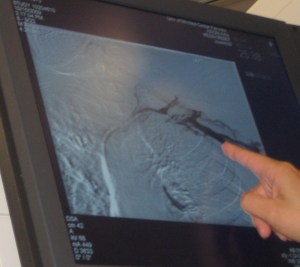

I was looking at old pictures tonight. I came across photos from one of my blood clots. In October 2009 I had a port-a-cath (or port for short) in my arm. A port is an implantable device under the skin used for the delivery of I.V. medication or blood draws. I was noticing that once in a while my hand and arm would turn purple, not for very long but enough that it was bothering me. It felt like I had a rubber band around my arm. After some time it started to get worse. The thing was everytime I was near a doctor my arm was just fine. I tried to figure out what would trigger it but couldn’t. It got to a point we had to make a of trip to the emergency room. When we arrived the E.R. doctor finally saw the purple hue I was talking about. He ordered some tests, but everything came back normal so they sent me home. Another week passed, my arm started to turn purple more often and for a longer period of time. I demanded they do some further investigating. Your arm shouldn’t turn that color without an explanation. The next morning I had an appointment. I’m laying on the table looking at the monitor as they inject dye into my my vein. Are you kidding me? The flow just stopped! Change of plan for my day, I ended up having an angioplasty. They thread up a device with a balloon at the end. Then blow up the balloon with the intent to stretch the vein enough to have blood flow again. They pumped up the balloon three times and then re-checked with the dye. YAHOOO it worked!

The photo on the left shows where the blood flow stopped, left of the finger. The photo on the right shows normal blood flow again. Thank goodness we did more investigating. I don’t want to think about problems that I could’ve had. We ended up taking out the port. I ended up with another port later on but that story can be another night.